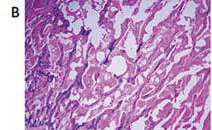

В рамках гранта РНФ «Экспериментальное изучение нейропротективных свойств современных сахароснижающих препаратов» выполнено экспериментальное исследование инфаркт-лимитирующего действия и влияния на неврологический статус арГПП-1 разной продолжительности действия (лираглутида, семаглутида, дулаглутида), а также иНГЛТ-2 разной степени селективности (эмпаглифлозина и канаглифлозина) у животных без СД с транзиторной фокальной ишемией головного мозга. Установлено, что все препараты обладали сопоставимой способностью сокращать объем повреждения головного мозга, однако только арГПП-1 способны уменьшать выраженность неврологического дефицита.

Anna Murasheva, Oksana Fuks, Natalya Timkina, et al. SGLT-2 Inhibitors’ and GLP-1 Receptor Agonists’ Influence on Neuronal and Glial Damage in Experimental Stroke // Biomedicines. — 2024. — Vol. 12, № 12. — 2797. IF 4,1. DOI: 10.3390/biomedicines12122797. Режим доступа: https://doi.org/10.3390/biomedicines12122797